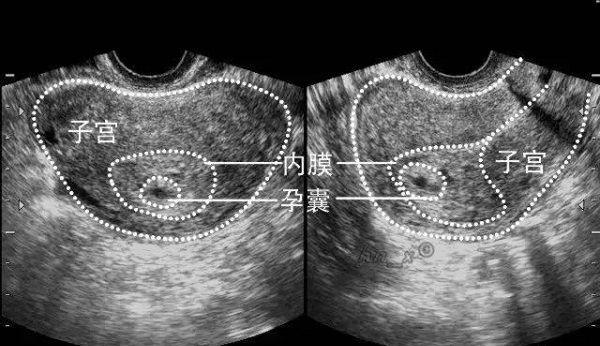

正常情况下,女性通过试管婴儿技术怀孕后6-8周的时候,就可以通过B超看到孕囊有胎心、胎芽的出现。如果在孕囊中没有发现胚胎组织的话,就代表是空囊。

试管出现空囊也就是说女性在怀孕后,由于胚胎的质量不佳,导致孕囊中没有胎心胎芽的生长发育。女性在怀孕期间身体会出现不同程度的变化。当女性怀孕初期出现空囊也会出现比较明显的症状和表现。